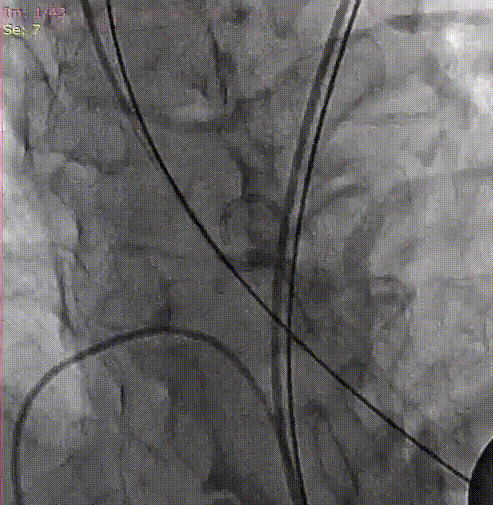

手术关键步骤

A.预扩张,并同时行主动脉造影

B. 冠脉保护:导丝、球囊、Guidezilla、位于LAD;Guiding回撤至升主动脉适当位置

C. 应用交界贴合技术调整人工瓣膜,标准位释放瓣膜并行释放后造影

D. 瓣膜释放后造影显示瓣膜位置良好

E.后扩张

F. 最终造影显示瓣膜位置良好冠脉开口血流正常,撤出冠脉保护